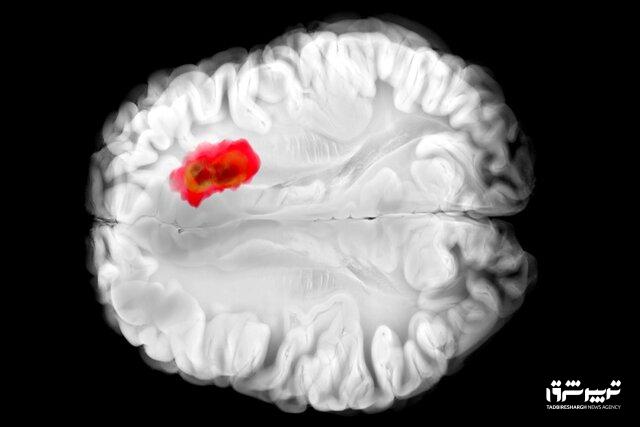

کشف دارویی برای مبارزه با کشندهترین سرطان های مغز

تصور میشود که همین آنزیم در سرطانهای مغزی گلیوبلاستومای تهاجمی نقش دارد. این درک جدید از «هیدرالازین» میتواند راه را برای درمانهای جدید سرطان هموار کند و همچنین اثربخشی دارو را برای اهداف فعلی آن بهبود بخشد.

مطالعات قبلی نشان دادهاند که تومورهای گلیوبلاستوما اغلب سرشار از ADO هستند و آن را برای تولید ماده شیمیایی به نام هیپوتائورین(hypotaurine) میربایند که به سلولهای سرطانی کمک میکند تا گسترش یابند، برای مدت طولانیتری زنده بمانند و فشار را تحمل کنند.

در آزمایشهایی که با سلولهای گلیوبلاستومای انسانی انجام شد، «هیدرالازین» با مسدود کردن ADO رشد تومور را متوقف کرد.